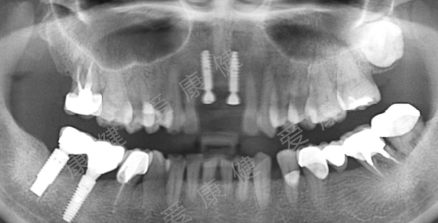

種牙步驟及結構如⑧

①種植牙是在缺牙位置植入人工金屬釘,等到金屬釘和牙槽骨長好了再做上麵的牙冠連接修複。

種牙後需要定期複診拍片了解種植牙情況